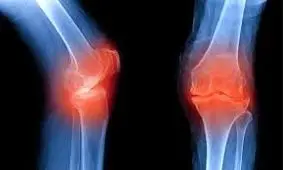

عضو هیئت علمی دانشگاه علوم پزشکی شهید بهشتی در خصوص انواع آرتروز و روشهای درمانی این بیماری توضیحاتی ارائه داد و بر…

میلیون ها نفر در سراسر جهان از آرتروز رنج می برند. در ادامه شما را با حقایق قابل توجهی درباره این مشکل شایع سلامت آشنا …